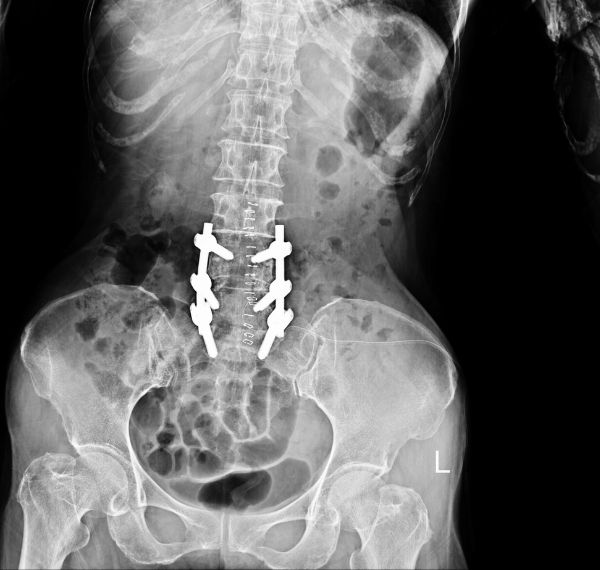

Spine Surgery (Discectomy/Laminectomy)

Surgical relief of nerve compression in the spine.

Who it’s for: Individuals with chronic back pain or herniated discs.

Key Benefits: Relieves pressure, improves posture, and restores spinal balance.